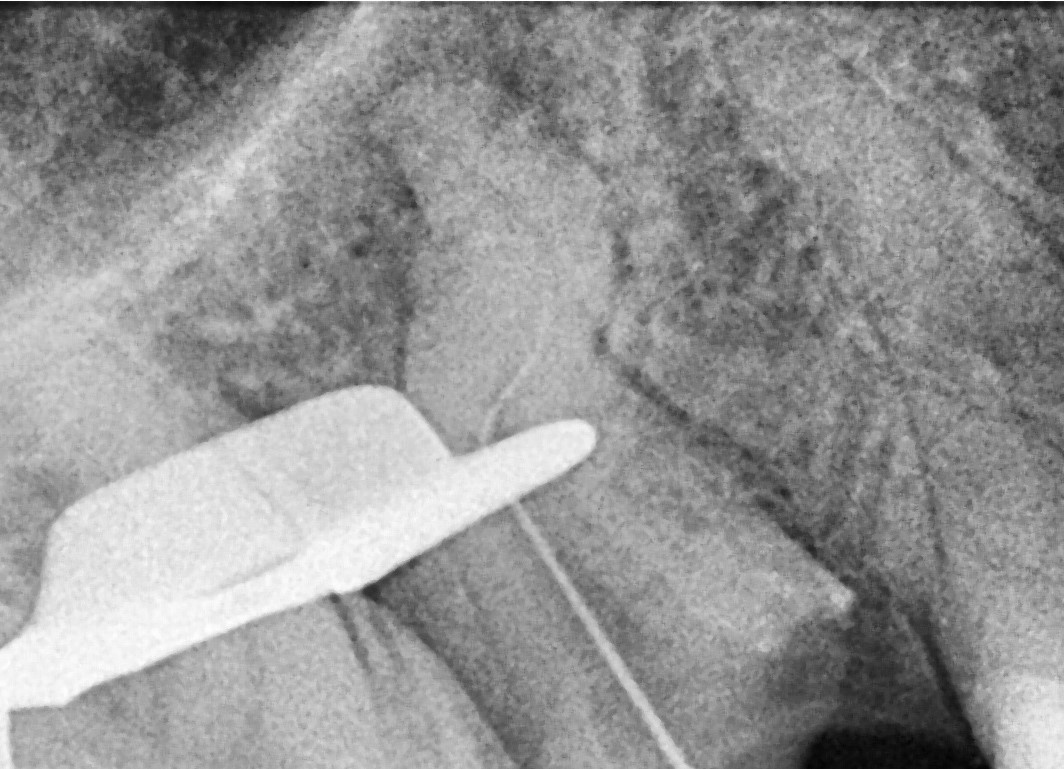

• In the palatal canal, the 10/07 “Opener” file from the SuperSystem Advanced Kit was used at 250 rpm and 1.5 Ncm torque, progressing to the middle third.

Following irrigation, 17/05 file was used at the same settings to reach the apex.

Working length was confirmed using a #06 K-file.

Canal enlargement was completed with the Perfect Advanced Kit 17/05 file (images 3 and 4).